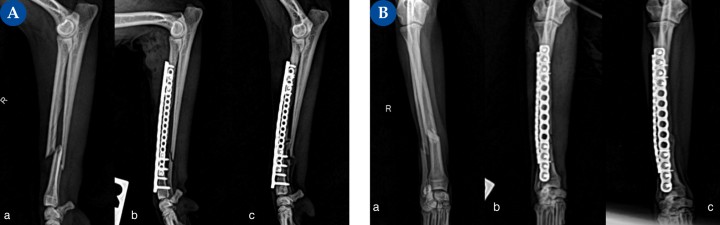

(A) Proyección mediolateral, (B) Proyección craneocaudal. Fractura diafisaria compleja de radio en un pomerania de 2,3 kg.(a) Fractura diafisaria compleja de radio. Además de presentar una fractura oblicua corta con un pequeño fragmento óseo (no reducible), la porción de radio proximal al foco primario presenta una fractura segmentaria espiroidea no desplazada.&nbsp;(b) Se realizó reducción abierta y fijación interna mediante un implante principal en la cara craneal, del radio, consistente en una placa bloqueada multiorificio poliaxial de titanio con cuatro tornillos bloqueados de 1,5 mm por&nbsp;fragmento, y como complemento una placa bloqueada de titanio, multiorificio, en la cara lateral, con dos tornillos bloqueados de 1,2 mm&nbsp;por fragmento. La distribución de los tornillos se realizó en los bordes más proximal y distal de ambas placas, dejando el centro libre. En un sistema de placas ortogonales, la posición de los tornillos no afecta a la resistencia al doblado o compresión, y levemente a la torsión.<sup>6</sup>(c) Evolución de la consolidación ósea a las 7 semanas postoperatorias.

(A) Proyección mediolateral, (B) Proyección craneocaudal. Fractura diafisaria compleja de radio en un pomerania de 2,3 kg.(a) Fractura diafisaria compleja de radio. Además de presentar una fractura oblicua corta con un pequeño fragmento óseo (no reducible), la porción de radio proximal al foco primario presenta una fractura segmentaria espiroidea no desplazada. (b) Se realizó reducción abierta y fijación interna mediante un implante principal en la cara craneal, del radio, consistente en una placa bloqueada multiorificio poliaxial de titanio con cuatro tornillos bloqueados de 1,5 mm por fragmento, y como complemento una placa bloqueada de titanio, multiorificio, en la cara lateral, con dos tornillos bloqueados de 1,2 mm por fragmento. La distribución de los tornillos se realizó en los bordes más proximal y distal de ambas placas, dejando el centro libre. En un sistema de placas ortogonales, la posición de los tornillos no afecta a la resistencia al doblado o compresión, y levemente a la torsión.6(c) Evolución de la consolidación ósea a las 7 semanas postoperatorias.